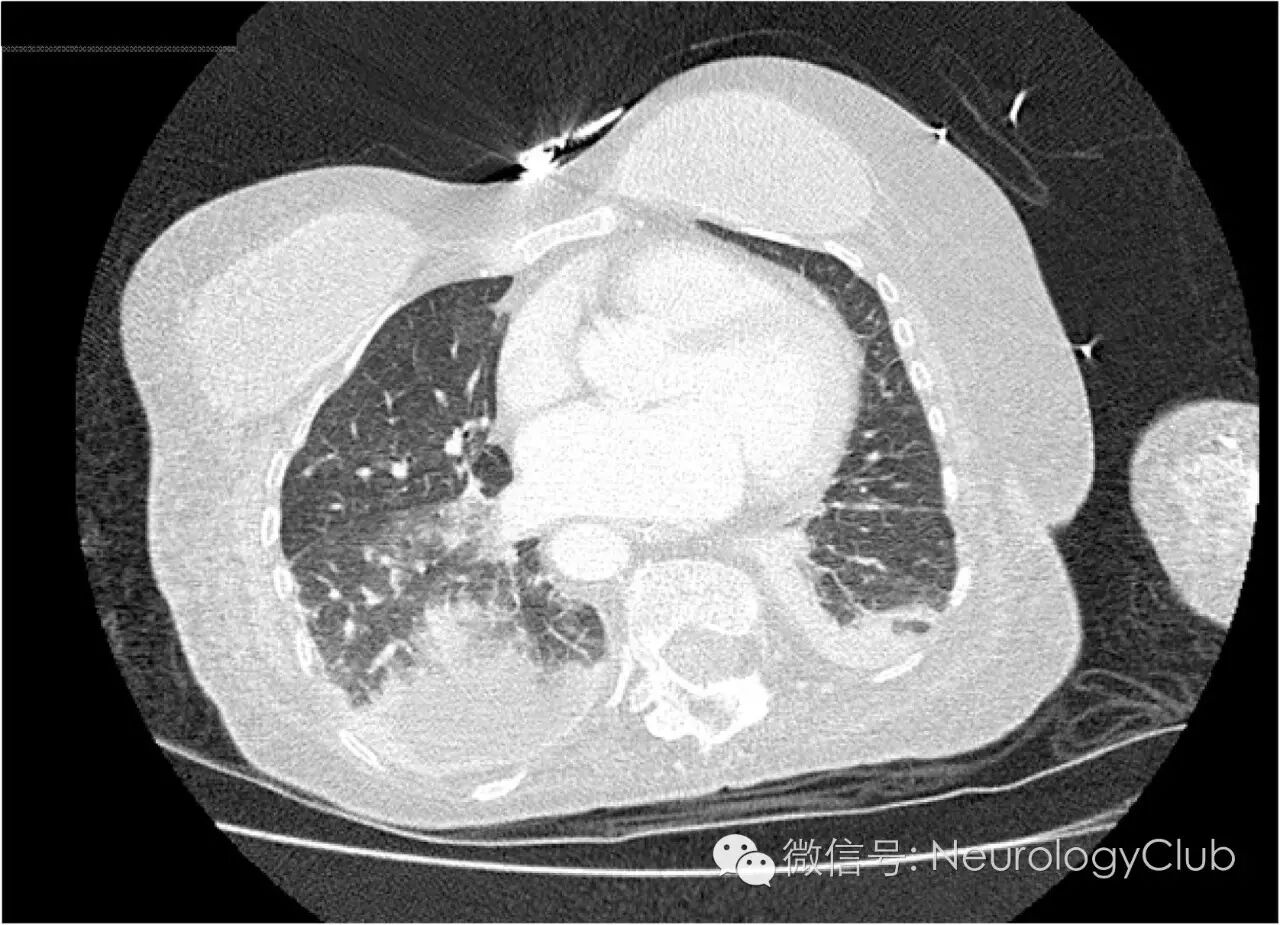

患者症状改善不佳。入院第22天行全结肠切除及回肠末端造口术。术后转至ICU继续治疗。胸部CT(图1)提示两肺渗出,胸腔积液,考虑呼吸机相关性肺炎,予万古霉素治疗。住院期间血培养阴性。痰培养提示寡养单胞菌,偶可见烟曲霉菌。抗生素调整加用伏立康唑,后改为泊沙康唑和美罗培南。

(图1:入院第37天胸部CT提示双肺渗出,胸腔积液)